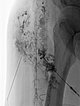

Image of direct lymphography with water-soluble contrast medium in direct puncture technique under sonographic guidance.

Here, it was possible to puncture the dysplastic, dilated lymphatic channels of the lymphatic malformation in the subcutaneous tissue several times.

Picibanil (OK-432) was then injected into these channels as a sclerosing agent to seal the cutaneous dysplastic lymphatic channels via the inflammation.

Lymphography in direct puncture technique under sonographic guidance.

The subcutaneous lymphatic vessel system is severely dysplastic, partially enlarged and showing bizarre net-like dilation. Normal lymphatic vessels are significantly smaller.

Again, picibanil (OK-432) was injected for inflammation-induced lymphatic vessel sclerotherapy and skin sealing.